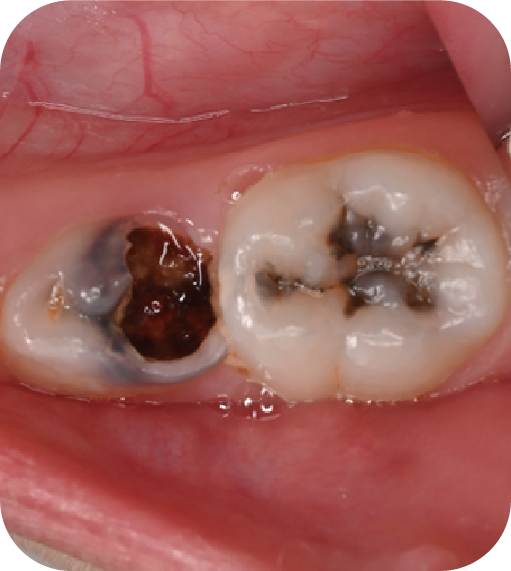

后磨牙,也就是大牙咬合面上凹凸不平的裂隙,這就是“窩溝”。窩溝有很多形狀,有的是狹長的裂隙形狀,還有的在牙齒深處又會分成幾條小溝。這些地方用牙刷很難深入清潔,于是就成了衛(wèi)生死角,細(xì)菌特別喜歡在里面生存,不斷產(chǎn)酸腐蝕牙齒,蛀牙就這樣產(chǎn)生了。如果我們用窩溝封閉把這些衛(wèi)生死角封起來,那既可以杜絕食物和細(xì)菌進(jìn)入窩溝內(nèi),也可以讓窩溝處的清潔變得更簡單,這就是做窩溝封閉的目的。同時它也是世界衛(wèi)生組織、國家衛(wèi)健委都推薦的防齲方法。